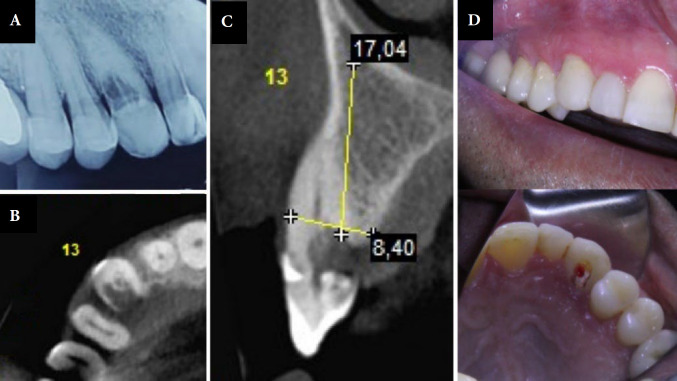

External cervical resorption is a condition that leads to the loss of hard dental tissues, including enamel, cementum, and dentin. Although it is an aggressive condition, its causes are not yet fully understood. The treatment of resorptions depends on their extent, location and the material used. When managing these lesions, the position of the bone crest and the ability of the periodontal tissue to adhere to the material after setting must be considered. This case report aims to demonstrate a clinical case of external cervical resorption which was treated by a proposed protocol that uses different dentin substitute restorative materials depending on the location of the resorptive area in relation to the bone crest. The success of this treatment depended on the correct use of materials and adequate tissue management. The combination of different materials has shown promising results in treating resorptions in both supra- and infra-osseous areas.